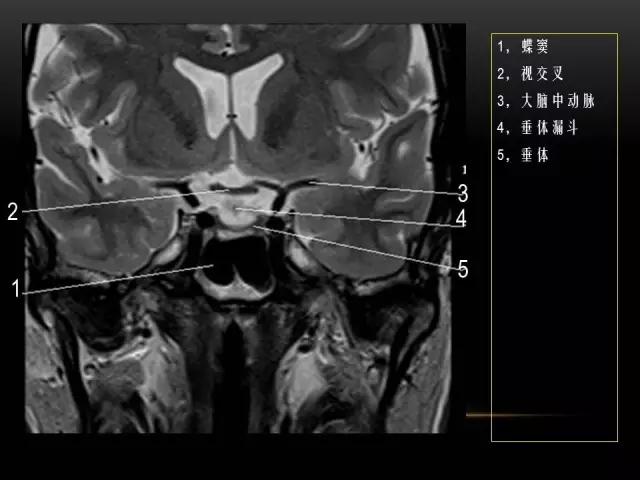

下文是在MRI下眼部及鼻窦的冠状位解剖图谱。